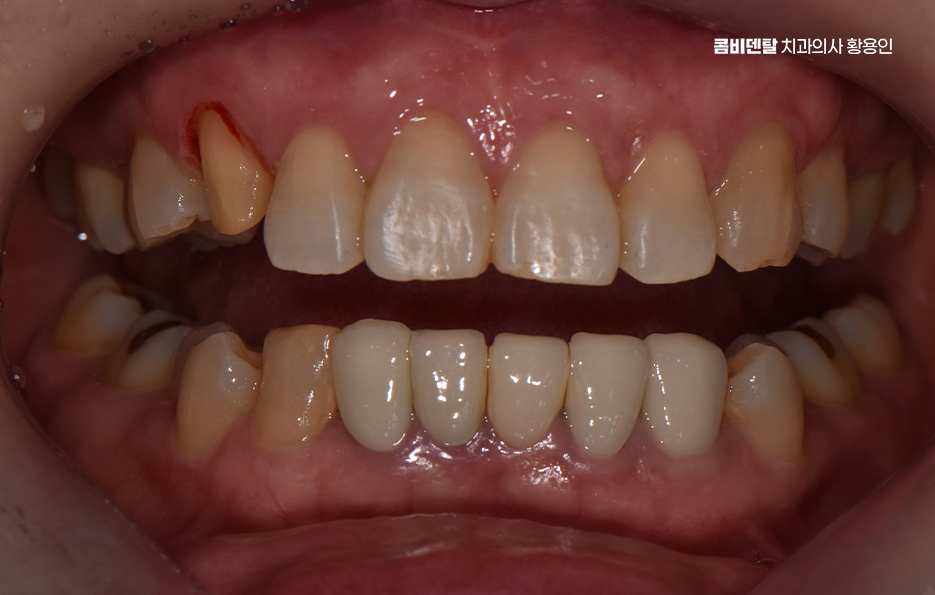

어릴 때는 송곳니가 나름의 포인트처럼 보였고, 웃을 때 조금 튀어나와 보이는 게 오히려 귀여운 느낌이라고 생각했을 만큼 별다른 불만도 없었고, 기능적으로도 별 신경 쓰지 않고 살았는데, 어느 날 그 송곳니에 작은 금이 간 걸 발견하면서부터 생각이 달라지게 됐어요, 처음에는 단순히 스치듯 지나가는 불편함이었고, 거울을 봐도 겉으로는 별다른 이상이 없었기에 그냥 피곤하거나 단단한 걸 씹다 살짝 충격을 받은 것뿐이겠지 하고 넘겼어요, 그런데 시간이 지나면서 그 송곳니 주변에 묘한 감각이 생기기 시작했고, 특히 찬물이나 단 음식이 닿을 때마다 찌릿한 시림이 점점 더 자주 찾아오면서 단순한 문제가 아니라는 걸 실감하게 됐어요. 정확히 언제, 어떤 이유로 그렇게 손상이 된 건지는 알 수 없었지만, 분명한 건 그동안 송곳니가 많은 역할을 해왔다는 거였어요, 다른 치아에 비해 뿌리도 깊고, 입꼬리 쪽에서 중요한 균형을 잡아주는 역할을 하다 보니 교합이나 저작 시에도 무게를 많이 견디는 위치인데, 그만큼 미세한 손상이 쌓이면 결국 파절이나 크랙으로 이어질 수 있다는 걸 나중에야 알게 됐어요, 다만 이미 치질이 약해진 상태라서 송곳니 크라운을 해야 했는데 송곳니는 눈에 잘 띄는 치아 중 하나인데, 거기를 깎고 덮는다는 게 쉽게 받아들여지진 않았고, 뭔가 내 얼굴 전체 인상이 바뀌는 건 아닐까 하는 걱정도 들었어요.

이처럼 송곳니의 손상은 비교적 눈에 잘 띄는 부위에 속하기 때문에 앞니 만큼이나 심미적인 치료가 중요한 부위이기 때문에 크라운 치료를 해야 한다면 심미성과 기능을 함께 고려한 치료가 중요할 수 있는데요

송곳니는 생각보다 입 안에서 중요한 역할을 하는 치아로 기능적으로는 앞니와 어금니를 연결해주는 다리 역할을 하고, 음식물을 자를 때나 씹을 때도 큰 힘을 발휘하는 치아이며 심미적으로도 얼굴 인상에 영향을 주는 위치에 있어서, 문제가 생겼을 때는 치료 방법을 신중하게 선택해야 하는 거예요

송곳니에 크라운 치료가 필요해지는 경우는 보통 충치가 깊게 진행됐거나, 외상으로 깨진 경우, 아니면 이미 신경치료를 한 후에 치아가 약해져서 파절 위험이 있을 때로 송곳니 크라운 치료를 고려할 때 치아의 손상 원인을 잘 분석하여 비슷한 문제가 재발하지 않도록 원인 파악과 개선 또한 무척 중요한데 아무리 치료를 잘 받아도 비슷한 문제가 빠르게 반복된다면 자연치아의 수명도 그만큼 빠르게 줄어들 수 있어요